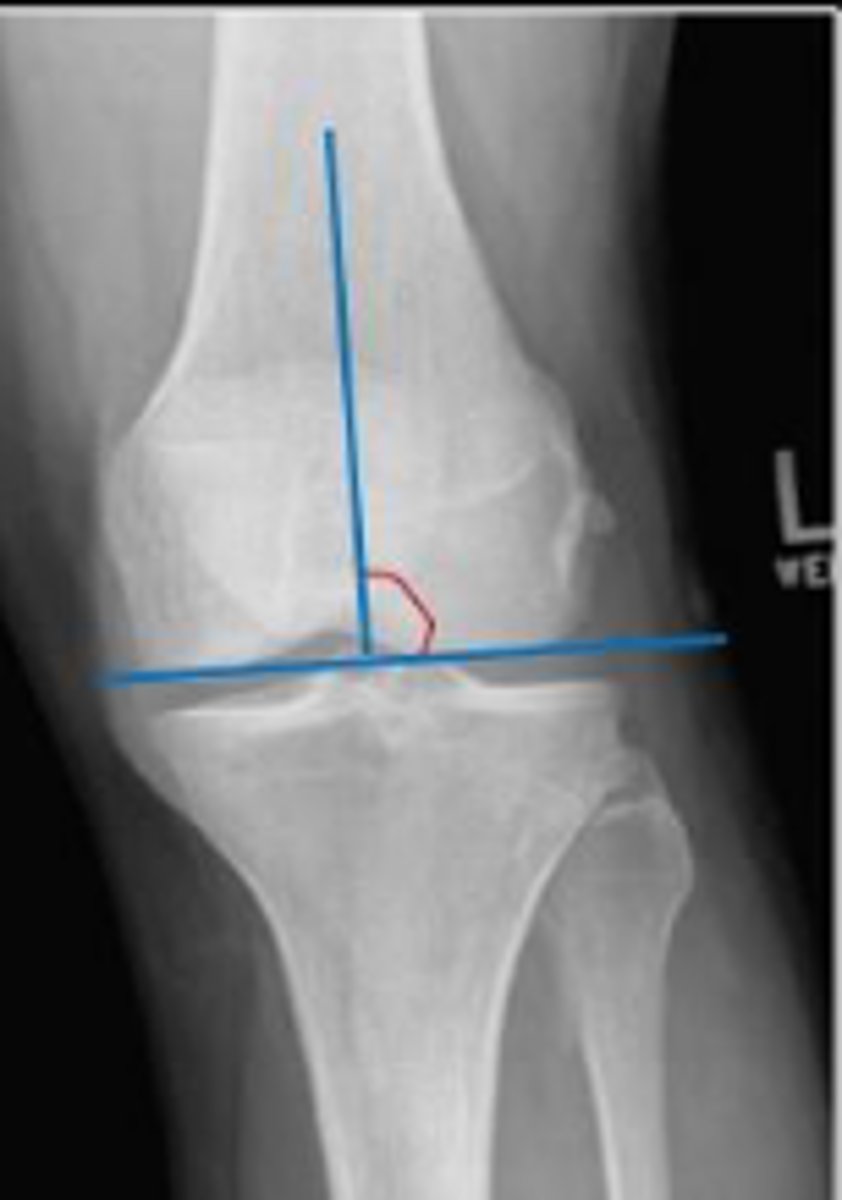

Femoral angle of the left knee

What is the name of the assessment?

Yes

Is this assessment within normal limits?